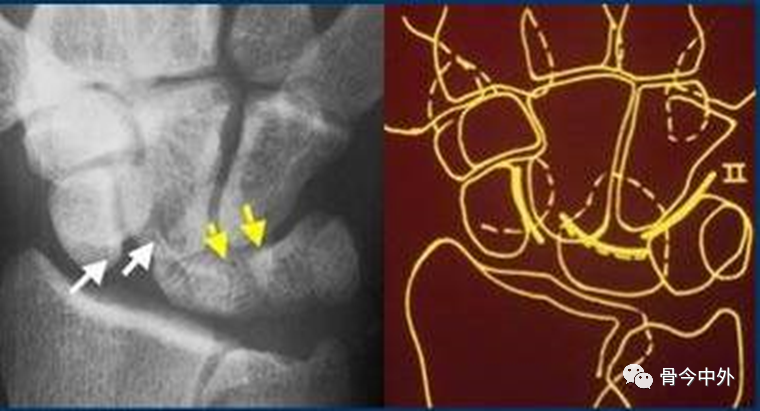

图19

弧线Ⅲ中断,上图显示头状骨-钩骨关节异常阶梯状改变。